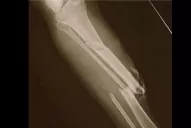

TREMENDO. El jugador fue retirado en camilla con enormes dolores. FOTO REUTER.

El alero de Indiana Pacers se fracturó la tibia y el peroné de la pierna derecha durante un partido de entrenamiento en Las Vegas el viernes por la noche y quedó descartado para la cita mundialista, que comienza a fines de agosto.

Al intentar taponar a un rival en un contraataque, George cayó con todo el peso de su cuerpo sobre su pierna derecha, que impactó en la base del tablero y se partió al instante